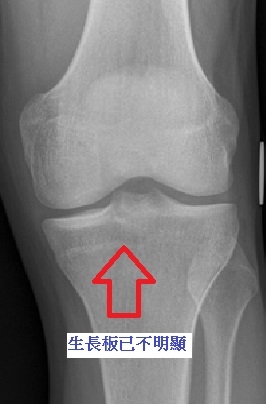

骨骼的拉長主要是看骨頭兩端的生長板存在與否,在生長發育時,這裡的骨骼細胞分裂,使骨頭得以成長,約在青春期結束時,生長板也癒合,此後就不太會再長高。

孩子進入青春期後,受到性賀爾蒙的刺激,會開始出現第二性徵(男::喉結、睪丸增大;女: 乳房發育、月經等),同時也會刺激骨骼生長快速長高,但患有性早熟的病童,因骨頭提早成熟,使生長板過快癒合,換句話說可能本來可以長5-6年,結果3-4年就不長了,因此病童成年後的身高會比預期的矮小。